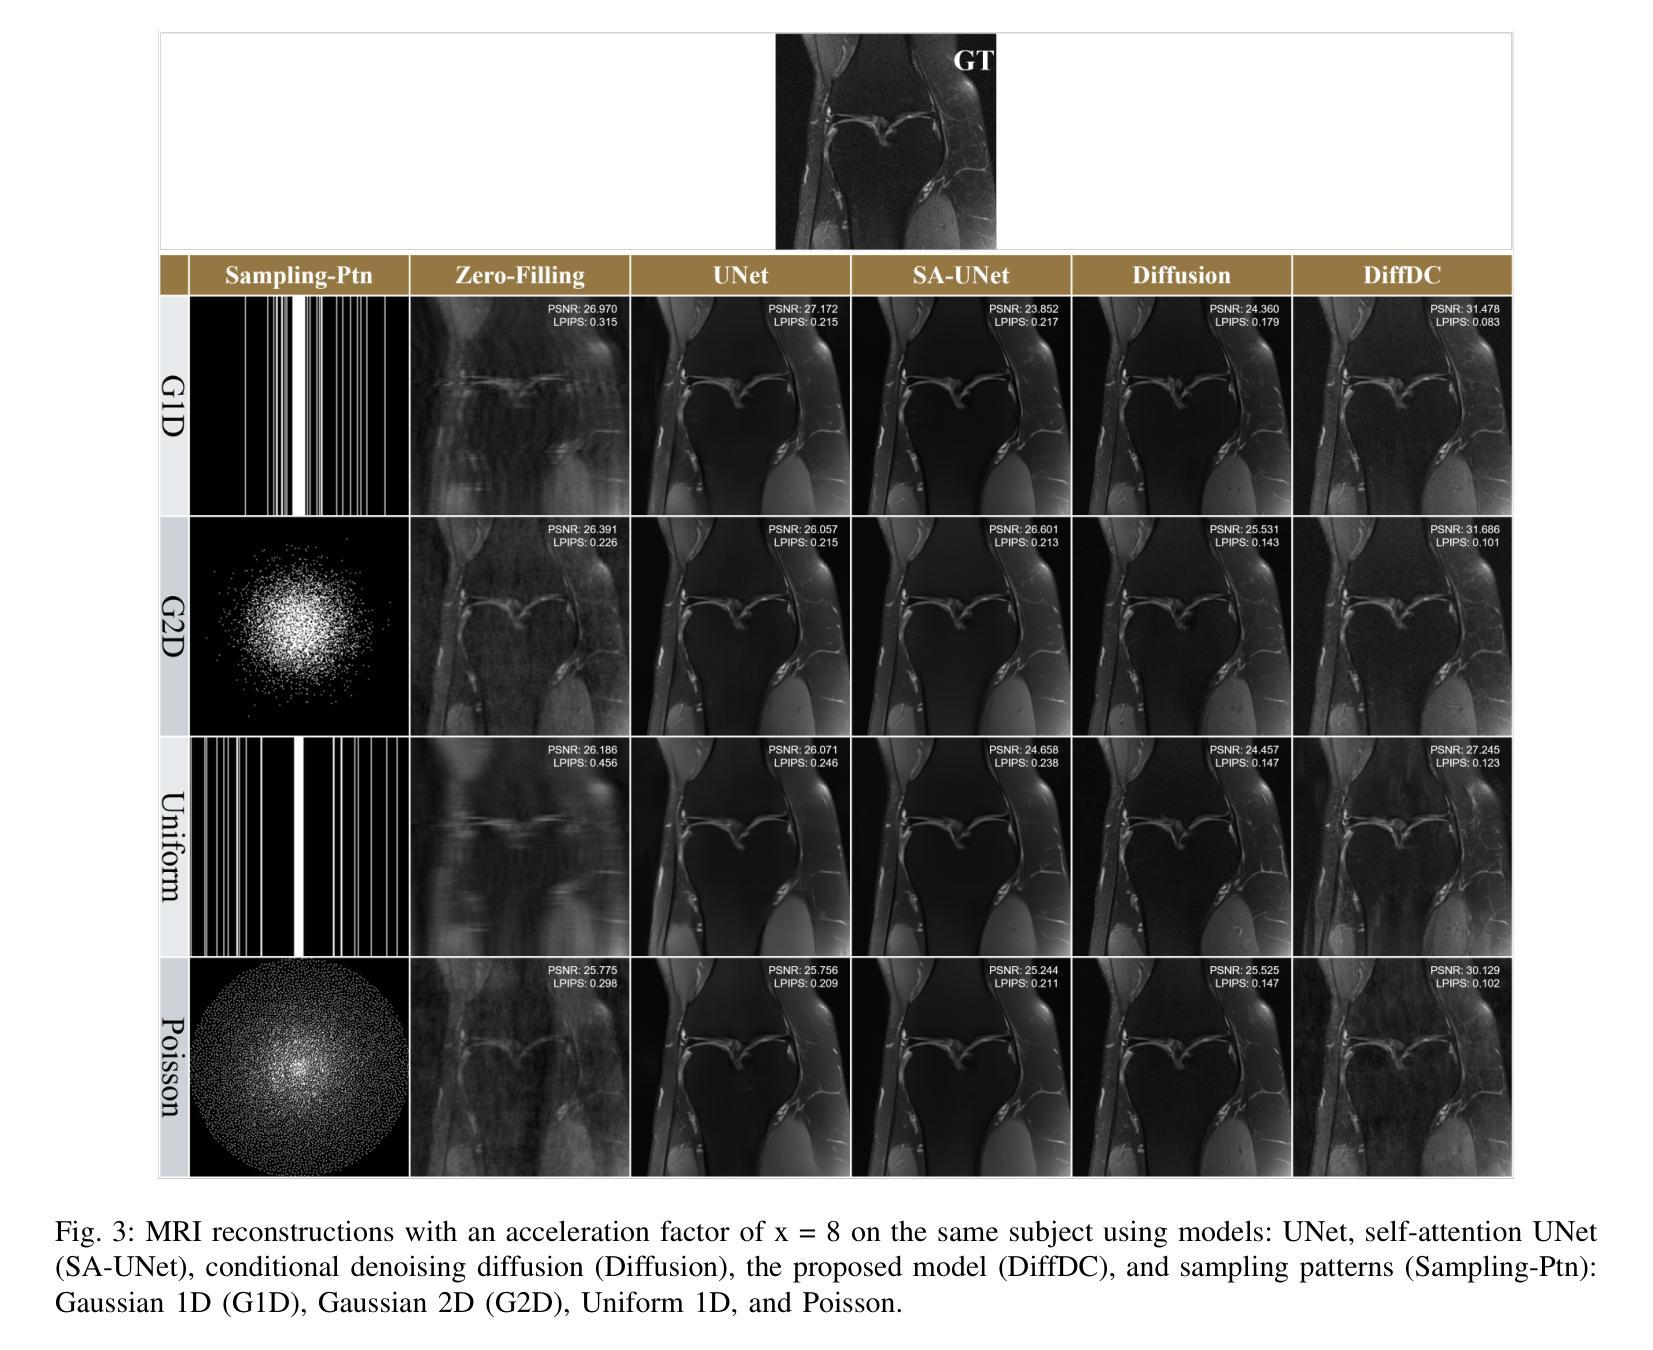

Conditional Denoising Diffusion Model-Based Robust MR Image Reconstruction from Highly Undersampled Data

Authors:Mohammed Alsubaie, Wenxi Liu, Linxia Gu, Ovidiu C. Andronesi, Sirani M. Perera, Xianqi Li

Magnetic Resonance Imaging (MRI) is a critical tool in modern medical diagnostics, yet its prolonged acquisition time remains a critical limitation, especially in time-sensitive clinical scenarios. While undersampling strategies can accelerate image acquisition, they often result in image artifacts and degraded quality. Recent diffusion models have shown promise for reconstructing high-fidelity images from undersampled data by learning powerful image priors; however, most existing approaches either (i) rely on unsupervised score functions without paired supervision or (ii) apply data consistency only as a post-processing step. In this work, we introduce a conditional denoising diffusion framework with iterative data-consistency correction, which differs from prior methods by embedding the measurement model directly into every reverse diffusion step and training the model on paired undersampled-ground truth data. This hybrid design bridges generative flexibility with explicit enforcement of MRI physics. Experiments on the fastMRI dataset demonstrate that our framework consistently outperforms recent state-of-the-art deep learning and diffusion-based methods in SSIM, PSNR, and LPIPS, with LPIPS capturing perceptual improvements more faithfully. These results demonstrate that integrating conditional supervision with iterative consistency updates yields substantial improvements in both pixel-level fidelity and perceptual realism, establishing a principled and practical advance toward robust, accelerated MRI reconstruction.

Summary

本文介绍了利用扩散模型加速磁共振成像(MRI)的技术。传统的MRI采集时间较长,而扩散模型能够在保证图像质量的同时,通过学习方法加速图像采集。本文提出了一种结合条件去噪扩散框架和迭代数据一致性校正的新方法,将测量模型直接嵌入到每个反向扩散步骤中,并在配对欠采样-真实数据上进行训练。实验证明,该方法在SSIM、PSNR和LPIPS等指标上均优于最新的深度学习和扩散方法,尤其在感知改善方面表现更出色。